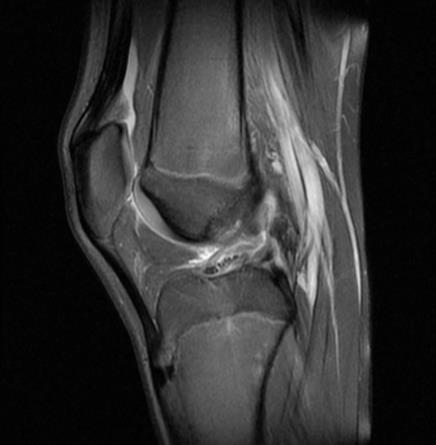

14岁的男孩是个爱运动的初中生,去年10月一次打篮球时,他不小心扭到了右膝,本以为休息几天就好,没想到疼痛一直没消。检查后才发现,问题出在膝盖里一块“不太一样”的软骨——他的外侧半月板天生不是常见的C形,而是更厚、更圆的“盘状”。

盘状半月板(Discoid Meniscus)是一种先天性解剖变异,指的是半月板的形状异常——

正常半月板呈新月形(C形),

而盘状半月板则更厚、更宽,形似半圆甚至满月。

这种异常结构不仅影响膝关节的生物力学,还更容易发生撕裂或引发疼痛,尤其在青少年运动损伤中需高度警惕。

手术时间:2024年12月11日

术式:关节镜下部分半月板切除 + 成形术(Saucerization,即“修整为C形”)

手术目标:保留半月板功能,恢复其负荷分散与缓冲作用。